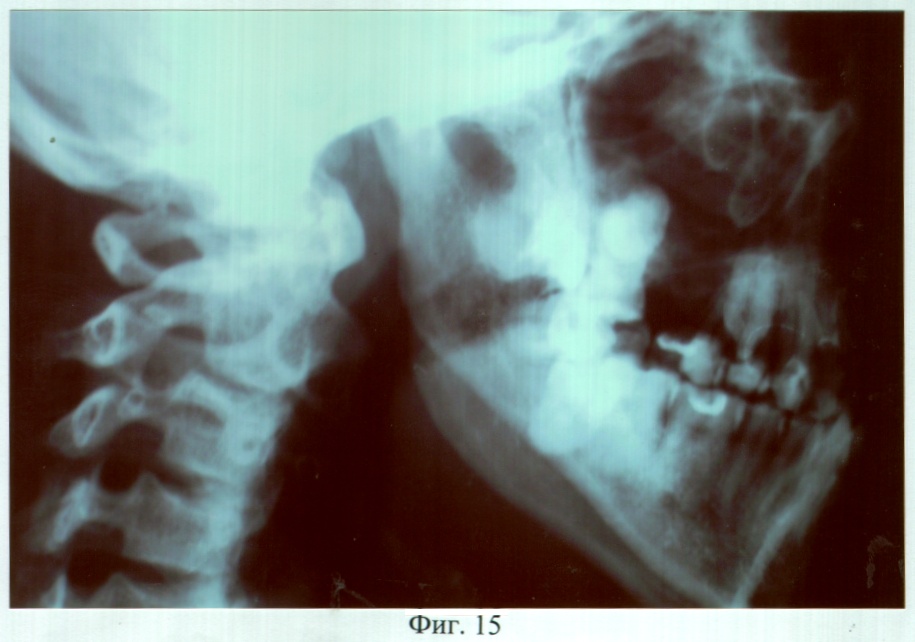

На фиг.15 – рентгенограмма больной С. до ортопедического лечения (правая латеральная проекция).

Пример 2. Больная С., 28 лет, обратилась в клинику ортопедической стоматологии с жалобами на наличие дефекта твердого и мягкого неба, затрудненное пережевывание пищи и попадание ее в полость носа, невнятность, гнусавость речи.

Из анамнеза: Ранее оперирована по поводу врожденной полной правосторонней расщелины верхней губы, твердого и мягкого неба, восемь раз – по поводу послеоперационного дефекта твердого и мягкого неба. Попытки изготовить зубочелюстной протез из акриловой пластмассы с целью восстановления нарушенных функций не привели к желаемому результату.

Объективно: нарушение конфигурации лица за счет правосторонней рубцовой деформации и западения мягких тканей верхней губы, крыла носа. В проекции отсутствующих 14, 13, 12 зубов определялся аркообразный дефект альвеолярного отростка правой верхней челюсти. Ротовая полость сообщалась с носовой и носоглоткой посредством четырех дефектов (переднего отдела твердого неба – эллипсовидной формы размером 10×5 мм, среднего отдела твердого неба – округлой формы размером 25×25 мм, заднего отдела твердого неба – эллипсовидной формы размером 10×5 мм, дистальной части мягкого неба – отсутствие язычка, медиальных краев правой и левой передних небно-язычных дужек). Слизистая оболочка, покрывающая костный изъян и прилежащие области, рубцово изменена. Зубная формула: 18, 17, 13, 11, 21, 22, 23, 24, 25, 27, 37, 36, 35, 34, 33, 32, 31, 41, 42, 43, 44, 45, 46, 47. В положении центральной окклюзии нижний зубной ряд сдвинут вперед (прогения), премоляры и моляры нижней челюсти язычными буграми перекрывали щечные бугры премоляров и моляров верхней челюсти, нижние фронтальные зубы располагались впереди верхних. Транспозиция 13 зуба в проекцию отсутствующего 15 зуба с оральной стороны альвеолярного отростка и его тортоанамалия на 80°, вестибулярное расположение 23 зуба.

DS: Операционный дефект твердого и мягкого неба, аркообразный дефект альвеолярного отростка правой верхней челюсти в проекции отсутствующих 14, 13, 12 зубов. Верхнечелюстная микрогнатия, частичная вторичная адентия III класса по Кенеди.

Адаптация к протезу наступила в течение семи дней, после чего больная отмечала удовлетворительное функциональное состояние зубочелюстного аппарата. Фонетическое обследование показало, что до ортопедического лечения нарушено произношение звуков – г, ж, к, п, р, т, ц, ч; k=5; U=21,3%. После протезирования нарушено произношение звуков – г, ж, к, р, ц; k=3; U=6,6%. При осмотре через 3 года больная жалоб не предъявляла, состояние протеза удовлетворительное. Морфологические исследования слизистой оболочки протезного ложа и рентгенография костей лицевого скелета, проведенные до и через 6, 12, 24 и 36 месяцев после протезирования, показали отсутствие признаков воспаления и прогрессирования атрофии.